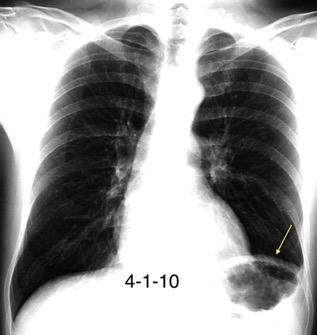

Autotrasplante de tejido esplénico al tórax tras trauma. (T. Penetrante más frecuente que cerrado)

Causas:

1. Trauma 2.Esplenectomía

3. Diseminación hematógena

4. ¿Hipoxia?

T1: Hipointenso

T2: Hiperintenso. Puede ser hipointenso. (Hierro)

Esplenectomía previa

Ferrer TM et al. Thoracic splenosis: History is the key. Respiratory Medicine Case Reports. 2017